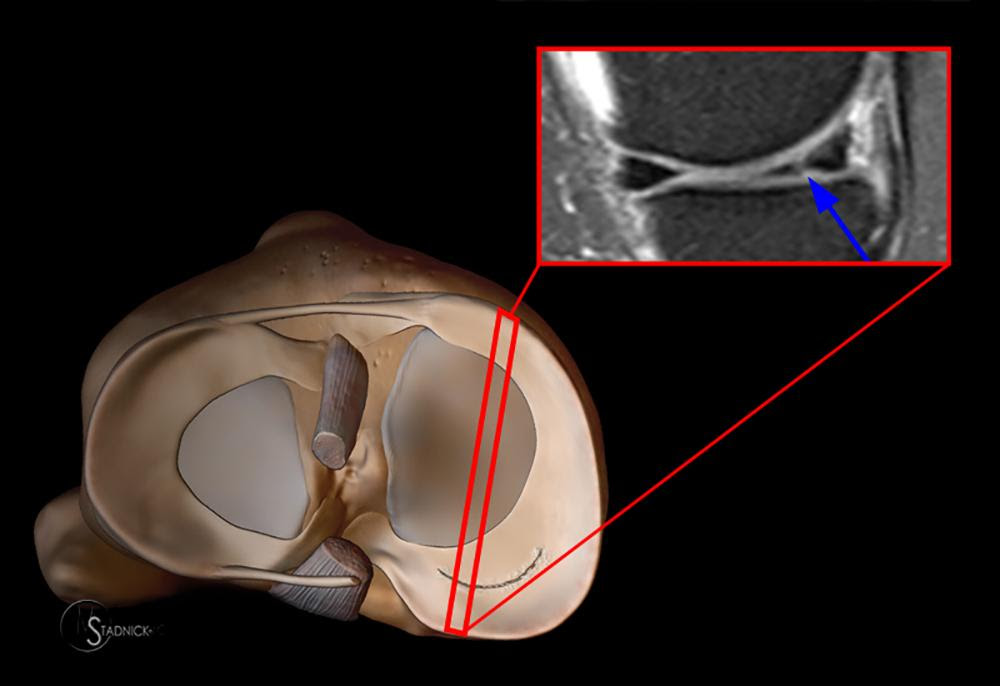

МРТ – позволяет увидеть хрящ в нескольких плоскостях, оценить состояние других околосуставных и суставных образований, что важно при наличии сомнений по поводу диагноза. МРТ при диагностировании проблем с мениском имеет точность до 95%. При сагиттальной плоскости хрящевая прокладка приобретает форму бабочки. При разрыве возникает симптом «двойной задней крестообразной связки», когда мениск прилежит к задней крестообразной связке и оказывается в межмыщелковой ямке бедренной кости.